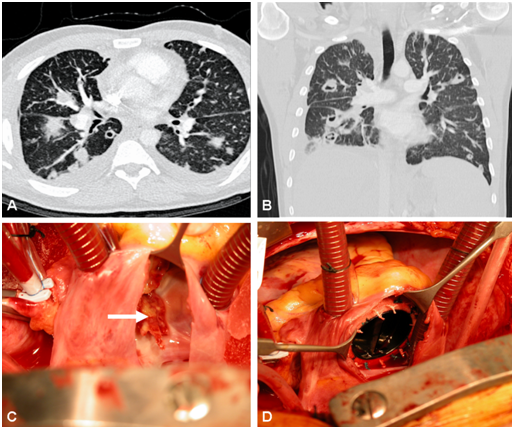

We report a 30-year-old male, intravenous drug abuser, referred with tricuspid valve endocarditis and bilateral multiple lung abscesses (Figure 1A) (Figure 1B). Over the preceding 2-months, he developed insidious symptoms of fatigue and dyspnoea. A transthoracic echocardiogram demonstrated severe tricuspid regurgitation and blood cultures grew methicillin sensitive Staphylococcus aureus. Initial treatment included combined broad-spectrum antibiotics. The pulmonary abscesses resolved following a period of microbial containment and pre-operative stabilization. He underwent a tricuspid valve replacement (Figure 1C) with a low profile 31mm mechanical prosthesis (ATS Open Pivot® Heart Valve, ATS Medical Inc, Minneapolis, USA) (Figure 1D). Following an uneventful postoperative course, the patient was discharged with endocarditis prophylaxis after 8 weeks and referred to a drugs rehabilitation facility. Three monthly follow-ups for 5years showed preserved bi-ventricular function with a functioning prosthesis at a constant mean gradient <3mmHg. During this period, the patient was free of narcotics and experienced no further pulmonary complications.

Figure 1A CT chest showing multiple lung abscesses in the horizontal plane.

Figure 1B Multiple pulmonary abscesses in the coronal plane on CT chest.

Figure 1C Intraoperative view of the destroyed tricuspid valve (white arrow marks the floating mass).

Figure 1D Well-seated low profile mechanical prosthesis in tricuspid position.